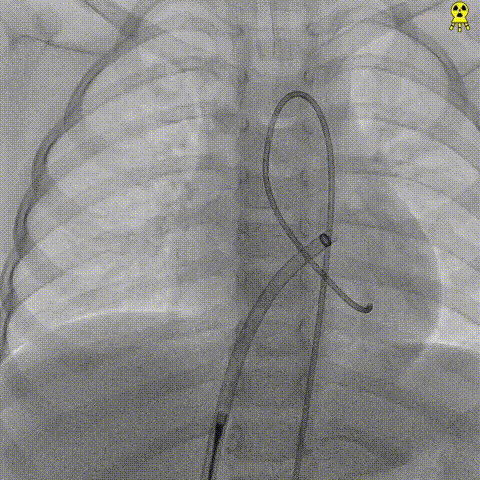

When faced with a complex congenital heart defect in a 2-year-old, how do we balance efficacy with lifelong safety? Meet a pediatric patient with a membranous ventricular septal defect (VSD) accompanied by pseudoaneurysm formation (basal width: 8.2 mm, shunt: 3.5 mm) and left ventricular false tendon—a rare and anatomically challenging scenario. Over two years of 5-time's follow-up, she was all diagnosed with typical membranous VSD, with a high-velocity left-to-right shunt (peak velocity: 5.1 m/s, gradient: 104 mmHg) and mild tricuspid regurgitation. Traditional metal occluders risk interfering with adjacent structures like the false tendon, potentially causing thromboembolism or valve dysfunction. But innovation stepped in: A memosorb fully biodegradable occluder was chosen. Why? 1. Adaptive design: Conforms to complex VSD anatomy, ensuring stability. 2. Degrades over time: Eliminates long-term risks of metal implants. 3. Preserves future options: No permanent hardware for a growing child. This case highlights the power of patient-centered innovation in congenital heart disease. Collaboration between imaging experts, interventional cardiologists, and families is key to navigating these high-stakes decisions.